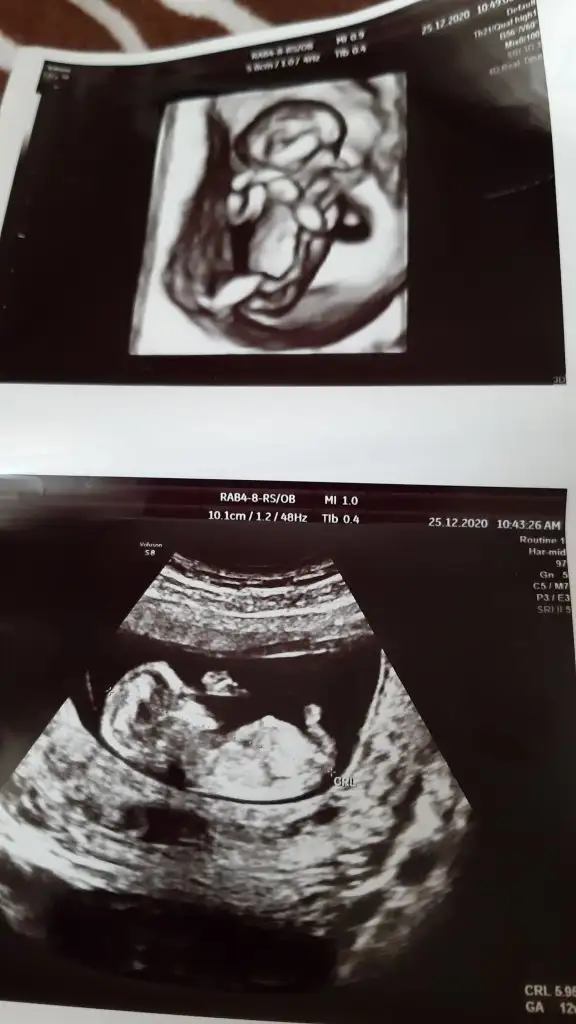

Ben anlamadım bunu canım 11 12 13 haftalar paylaşın tekrar bakıp çizim ☺️ yada varsa başka USG paylaşın

Bugüne kadar paylastiginiz usgler arkadaşınızın miydi 🙈 zaten son USG ile emin değildim o görünen nub ise erkek olabilir yazdim çok bozuk usg çünkü ☺️